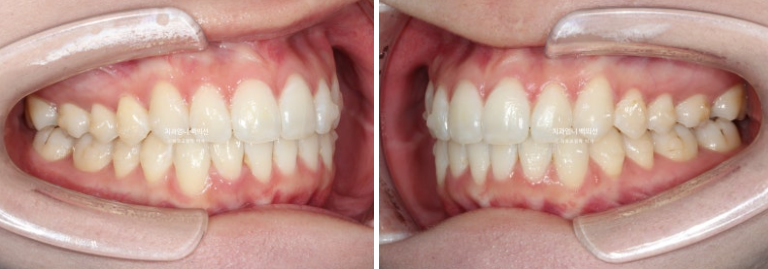

위 아래 치아중심선이 어긋나 있고 아래 앞니 하나가 솟으면서 뒤로 들어가 있습니다.

어금니 교합은 좋죠.

첫 세트 14개 장치를 모두 낀 후 모습입니다

중심선은 잘 맞고

원래 좋았던 어금니 교합은 잘 유지 되었고

배열도 좋습니다.

인비절라인라이트 재제작 기회가 1번 있지만 경과가 좋아 재제작 없이 마무리 했습니다.

중심선은 잘 맞고 과개교합도 좋아졌고 잇몸라인의 개선도 보입니다.

솟아있던 아래 앞니 덧니를 합입시켜 주변치아와 높이를 맞추었고 그 과정에서 잇몸라인도 자연스럽게 높낮이가 개선이 됩니다.

총 치료기간은 5개월 입니다.